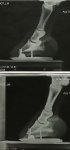

Any one had similar issues with happy field sound result..( My Ex driving horses) current owner is devastated, Vet says we have to wait and see, not field sound at moment, this all happened in last 6 weeks. If he is not field sound to retire, then the other option is PTS ..He is ID x Gypsy Va, 17h, age 18.

One Bute a day at moment. Not insured now. We have between us, owned him 11 years